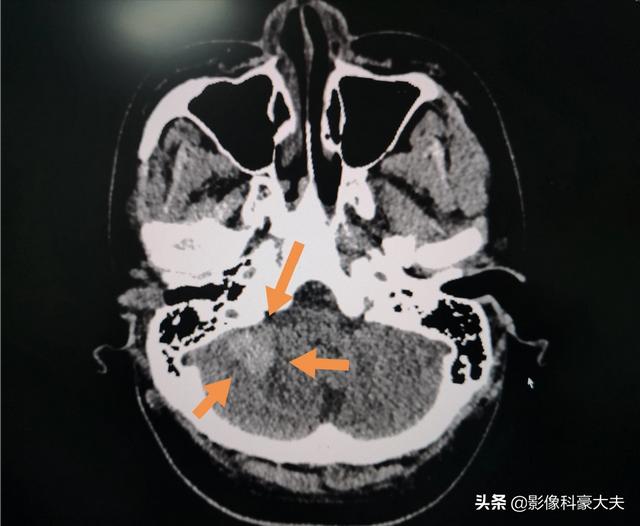

Und einige akute und kritische Patienten.Zum Beispiel massive Hirnblutung, massiver Hirninfarkt, Fremdkörper in der Luftröhre, Leber- und Milzprellung, Blutung bei Eileiterschwangerschaft, Aortenisthmusstenose, schwere Lungenentzündung und so weiter, die in einem Wettlauf mit der Zeit gerettet werden müssen! Nach der Untersuchung solcher Patienten wird der Arzt Spezialisten mit der vorrangigen Behandlung beauftragen, in kürzester Zeit einen Bericht erstellen, den behandelnden Arzt telefonisch benachrichtigen und so schnell wie möglich eine angemessene Behandlung einleiten, um die Hoffnung auf eine erfolgreiche Wiederbelebung zu erhöhen!。

Es handelt sich um einen 22-jährigen Jungen mit akuter Leukämie, der eine Kleinhirnblutung hatte, und wir haben innerhalb von 8 Minuten einen Bericht erstellt.

Sehen Sie dieses Bild? Der Prozess der Erstellung einer vollständigen CT-Diagnose ist so, als würde man versuchen, den problematischen Felsen aus einer dichten Masse ähnlich großer Felsen herauszufinden, einfach? Es ist schwindelerregend.

Natürlich gibt es Fälle, die dringlicher sind und in denen der Bericht dem Patienten sehr schnell ausgehändigt werden kann. Bei einem Patienten, bei dem ein hoher Verdacht auf eine Hirnblutung besteht, wird der Bericht wahrscheinlich relativ schnell nach der Durchführung eines Schädel-CTs an die Familie des Patienten ausgehändigt. Der Grund für die Schnelligkeit in diesem Fall ist, dass der Zustand des Patienten ernst ist und die Ergebnisse des Schädel-CTs sehr wichtig sind, so dass es verständlich ist, dass der Bericht in vielen Fällen dem Patienten schnell übergeben wird.